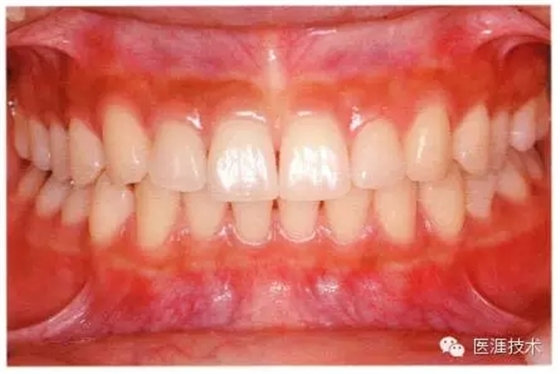

28歲女性的健康口腔內(nèi)部

圖為28歲女性,無特殊全身疾病,不抽煙。10年前來院就診保養(yǎng)3年,期間中斷過,現(xiàn)又開始。齲壞風(fēng)險高,當(dāng)初初診時已有好幾顆牙的鄰面有填充物,再填充了3牙的鄰面齲,現(xiàn)牙周組織健康。